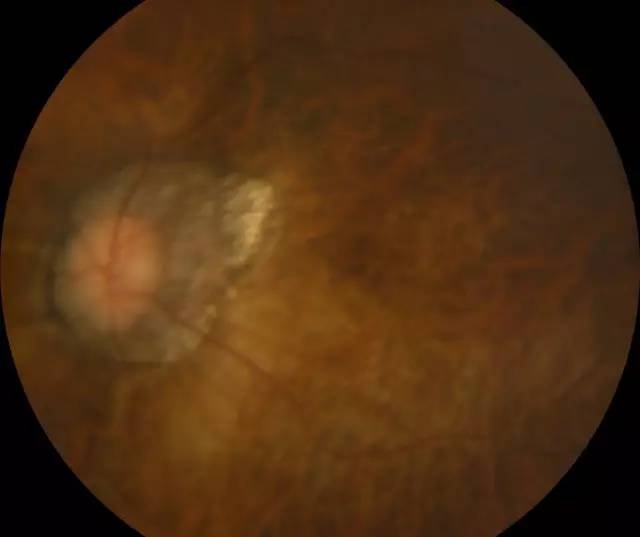

二天,赶上周末,家人陪着肖先生连忙赶到深圳牛八体育进行诊治。经过一系列检查,确诊肖先生为超高度近视裂孔性视网膜脱离,由于黄斑区视网膜全部脱离,必须要尽快做手术。

肖先生左眼术前眼底照相图